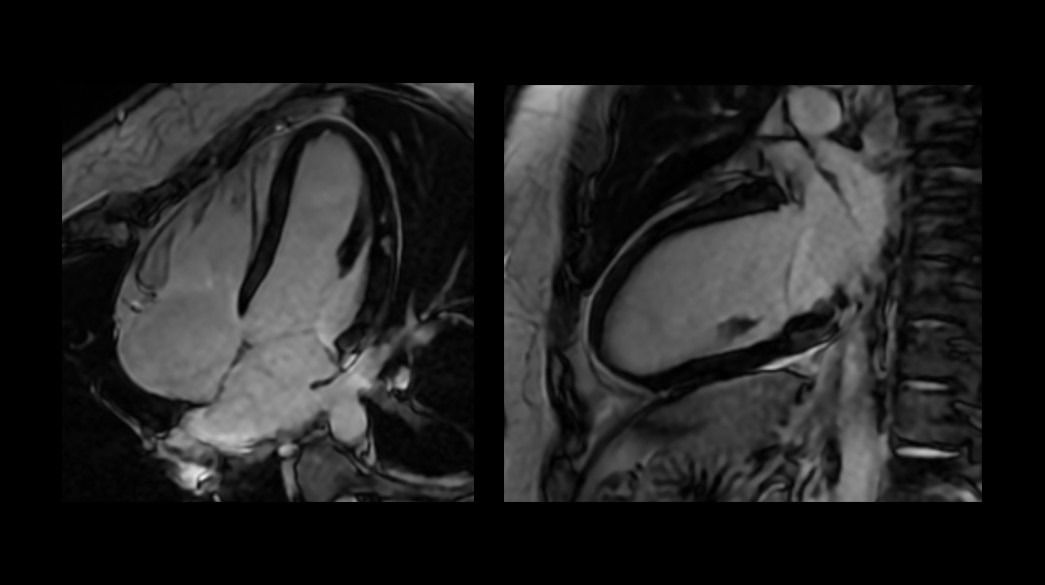

<p>FIESTA Cine</p>

Read case study ico-caret-right

<p>ViosWorks</p>

<p>3D Heart – compatible with AIR Recon DL</p>